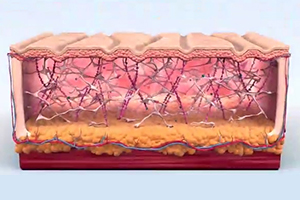

피부 표면과 평행한 3D 원통형 열기둥을 생성합니다. 최적의 피부 자극을 위해 6~70도의 열 온도를 5초간 진피층에 노출시킵니다.

-

Step 3.

시술 후 조직 검사 결과 진피 중간층의 콜라겐이 증가, 진피 탄력섬유(elastic fiber)가 탄탄하게 재정렬된 것을 확인됩니다.